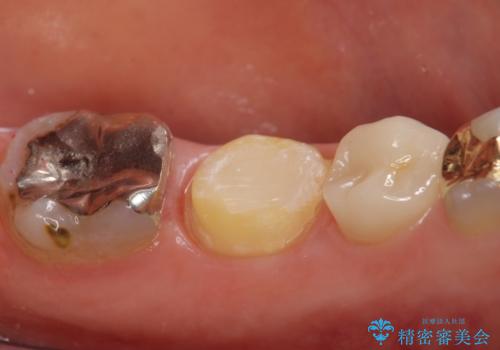

- 右下奥の歯茎がたまに腫れて膿が出るので診て欲しいといらっしゃった方の症例です。

診査の結果右下6の歯の神経が死んでいたため根管治療を行い、オールセラミッククラウンによる補綴を行いました。